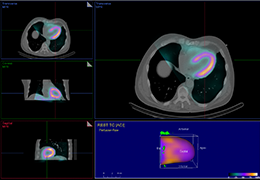

High-quality and fast 3D reconstruction and 3D rendering

Performs 3D reconstruction and volume rendering.

Multi-planar slicing.

Axis-aligned cropping with context.